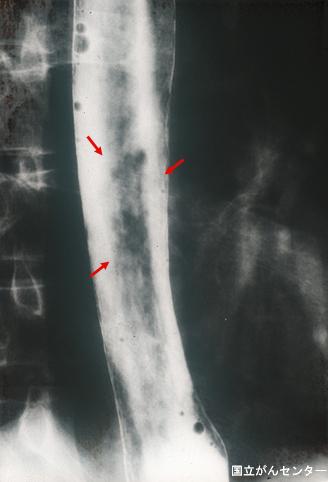

Criteria of Hist.ClassificationMalignant epithelial tumor/Squamous cell carcinoma

LocationEsophagus/Lower third

Technique, MethodX-ray

Macroscopic TypesType 0/IIc (IIc) Superficial depressed type

Size10 - 14

Depth of Tumor Invasionmuscularis mucosa

Multiple neoplasm in same organSynchronous